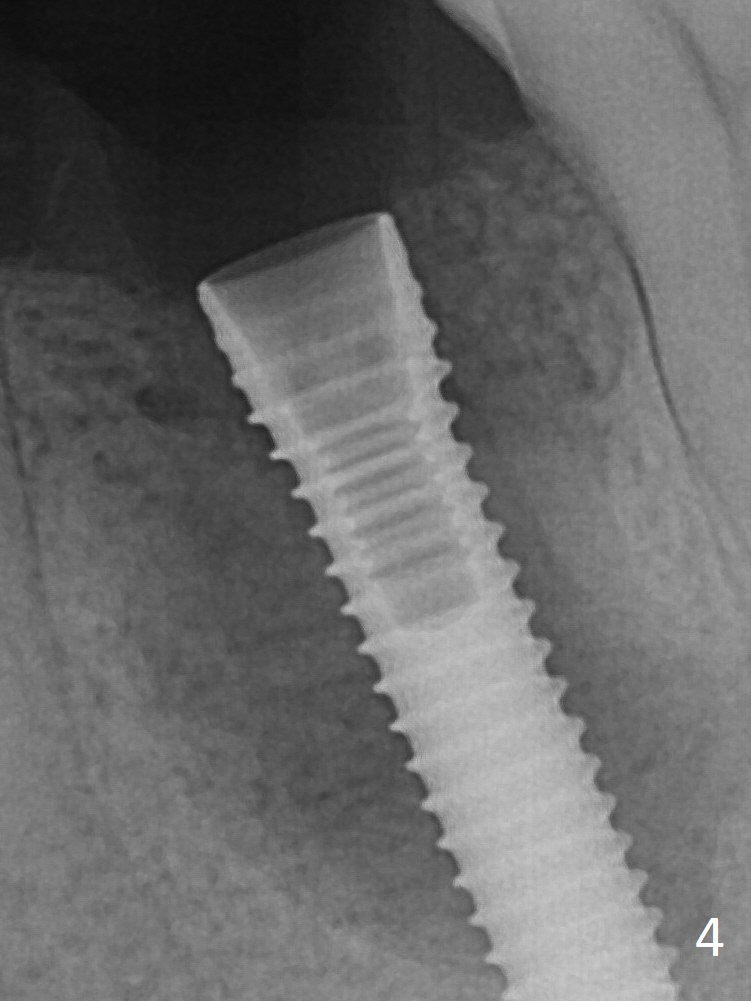

It appears that a 3.8x18 mm implant is not placed deep enough. Following 3-4 more turns of the implant and placement of a 5.5x4(3) mm abutment (Fig.5 A), allograft is placed (*).